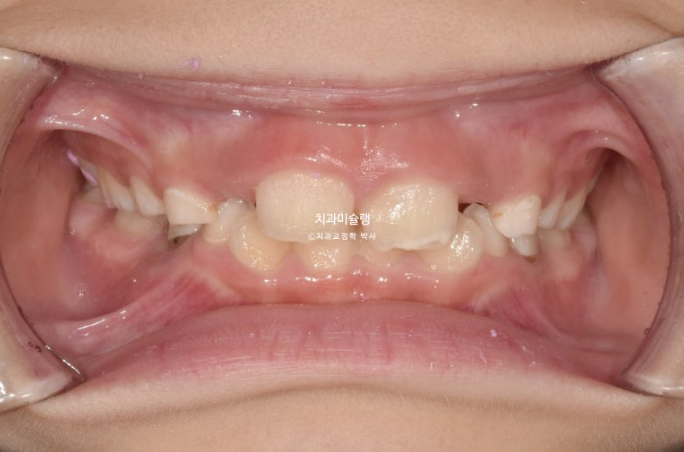

23년 10월, 교정치료를 위해 온 어린이 입니다.

앞니 두 개 높낮이 차이, 앞니가 깊게 물리는 과개교합이 보입니다.

앞니 네개 중 옆 앞니 즉 측절치가 나올 공간이 좁습니다.

아래도 마찬가지 입니다.

앞니가 벌써 삐뚤삐뚤 합니다.

송곳니가 나올때는 어떻게 될까요?

덧니 100% 예약입니다.

어린이 교정은 악궁확장을 통해 이가 날 공간을 넓히는 과정이 동반이됩니다.

인비절라인 퍼스트 치료에 들어갔습니다.